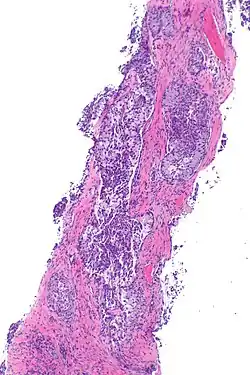

| Micrograph showing ALK positive lung adenocarcinoma. H&E stain. | |

Most lung carcinomas containing the ALK gene fusion are adenocarcinomas.